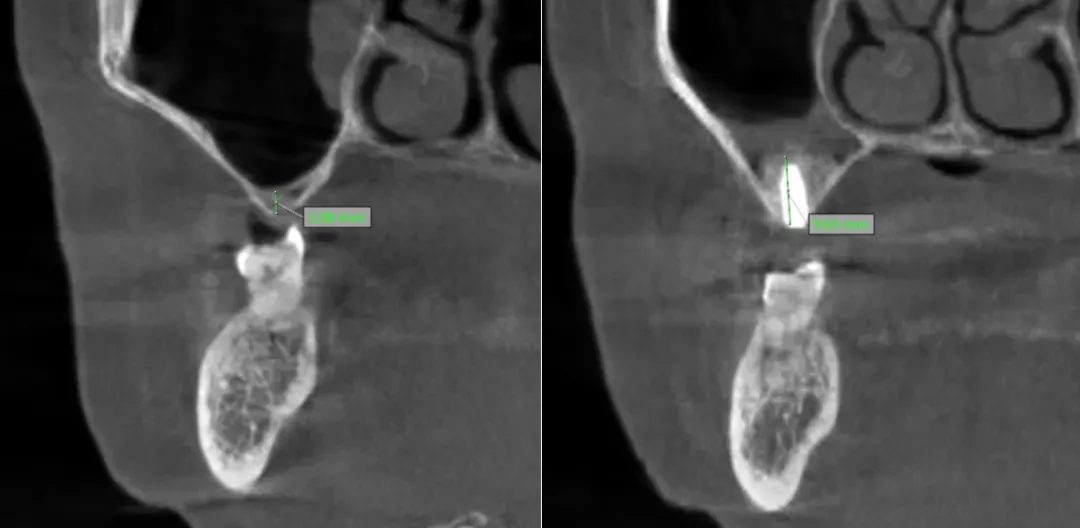

種植牙成功的核心在于充足的骨量支撐,對(duì)于骨量嚴(yán)重不足的患者,術(shù)前精準(zhǔn)評(píng)估與科學(xué)規(guī)劃非常重要。延安市中醫(yī)醫(yī)院口腔科閆慧鑫主任帶領(lǐng)團(tuán)隊(duì),結(jié)合患者全身健康狀況、口腔功能需求及美學(xué)期待,運(yùn)用三維CBCT影像技術(shù)對(duì)頜骨進(jìn)行全方位、立體化掃描分析。通過(guò)精準(zhǔn)測(cè)量剩余牙槽骨的高度、寬度,明確上頜竇位置與形態(tài),同時(shí)模擬手術(shù)全過(guò)程與修復(fù)效果,最終為患者制定了上頜竇外提升同期種植體植入的個(gè)性化手術(shù)方案,讓每一份骨量都能得到充分利用。

術(shù)前骨高度? ? ? ? ? ??術(shù)后骨高度及種植體

手術(shù)中,閆慧鑫主任帶領(lǐng)團(tuán)隊(duì)將數(shù)字化導(dǎo)航技術(shù)、微創(chuàng)理念與精準(zhǔn)外科操作深度融合,在確保上頜竇開(kāi)窗完整、黏膜剝離無(wú)損的前提下,小心翼翼分離并提升上頜竇黏膜,再精準(zhǔn)植入骨材料以增加骨高度,為種植體植入創(chuàng)造理想條件,隨后順利完成了骨材料植入與種植體植入。